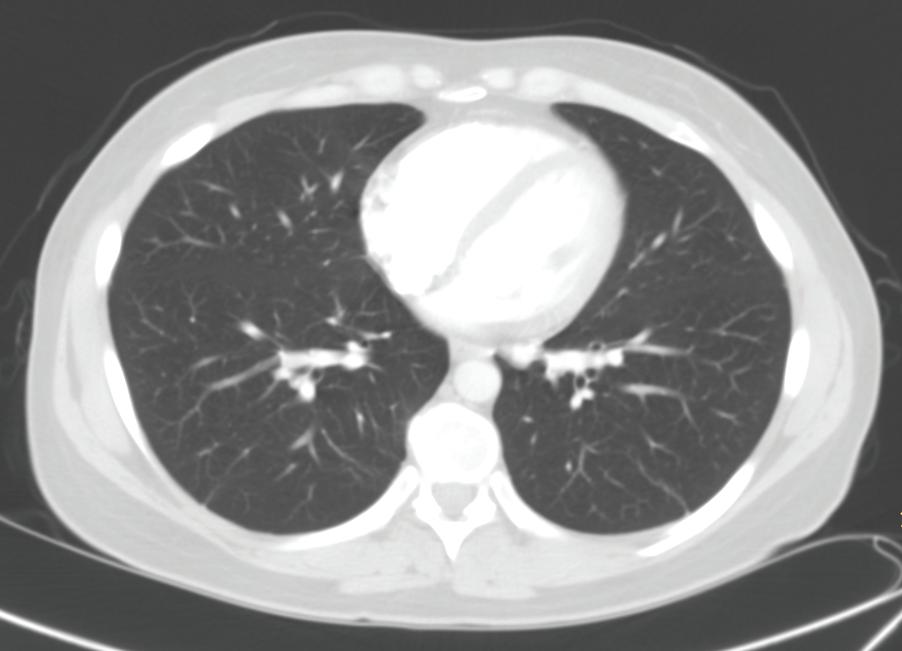

FIGURE 1-20 Three axial chest CT images using different window settings. The top image was made using a soft tissue window. In this image, the different soft tissue densities (note: muscles and intermuscular fat planes) and the bright contrast enhancement of blood in the heart are very conspicuous. The middle image was made using a lung window setting, in which lung markings, mainly pulmonary veins, are visible. The lower image was made using a bone window setting. With these window and level settings, you can see the distinction between marrow and cortical bone in the ribs.